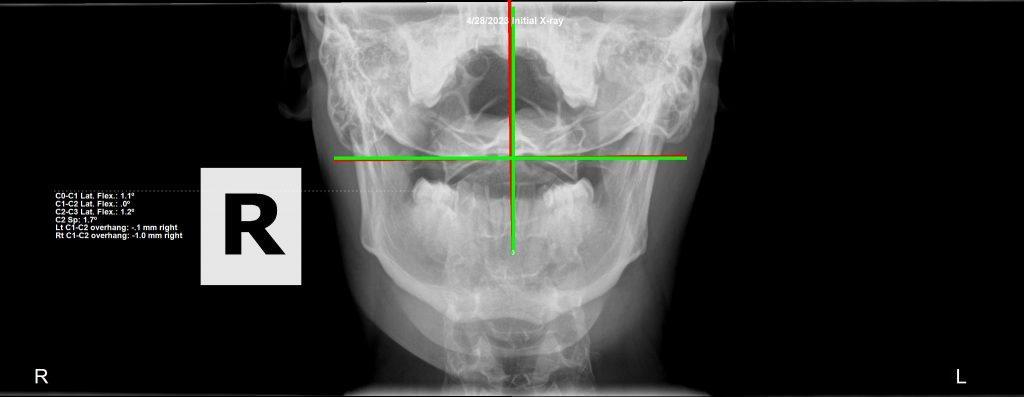

We have a 27 year old male who suffered an injury in the gym to his neck. He came to us suffering from headaches, double vision from a lazy left eye (that he never had before), facial pain and parasthesias, and parasthesias radiating into his arms. After 3 months of care, all of his symptoms had resolved, including his lazy eye. He was even showing signs of holding his adjustments. And then….. a series of events occurred that increased his stress levels significantly.

Now, all of these new issues are related. We are kinetic chains: everything connected through motion. As his spine has changed, specifically his pelvis, other areas of his spine appear to be worse on film, although functionally speaking, he is better.